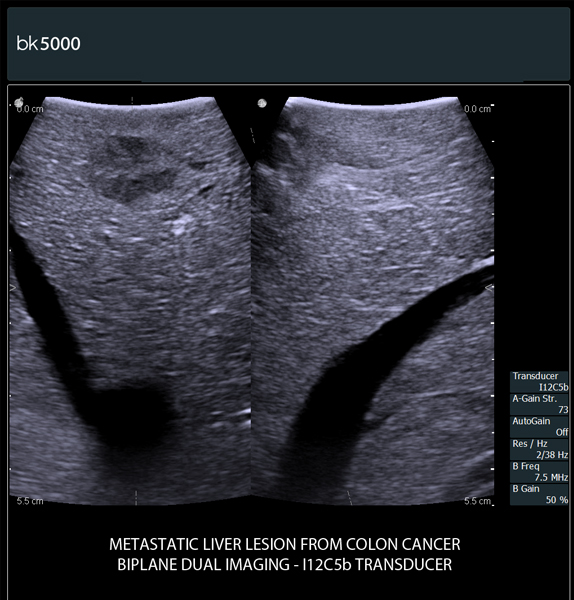

You know what you need, and you need it fast. That’s why the bk5000 is designed to deliver the high resolution images you count on quickly and efficiently. Whether you’re identifying margins of a lesion or making a general assessment of an area of interest, the bk5000 has the power and performance to meet your needs on your terms.

From the simplest diagnostic imaging to the most critical interventional procedures, every clinical situation has its own set of unique challenges. The bk5000 offers a full suite of innovative technologies and advanced controls and adjustments to help you achieve the best possible image quality, across many applications.